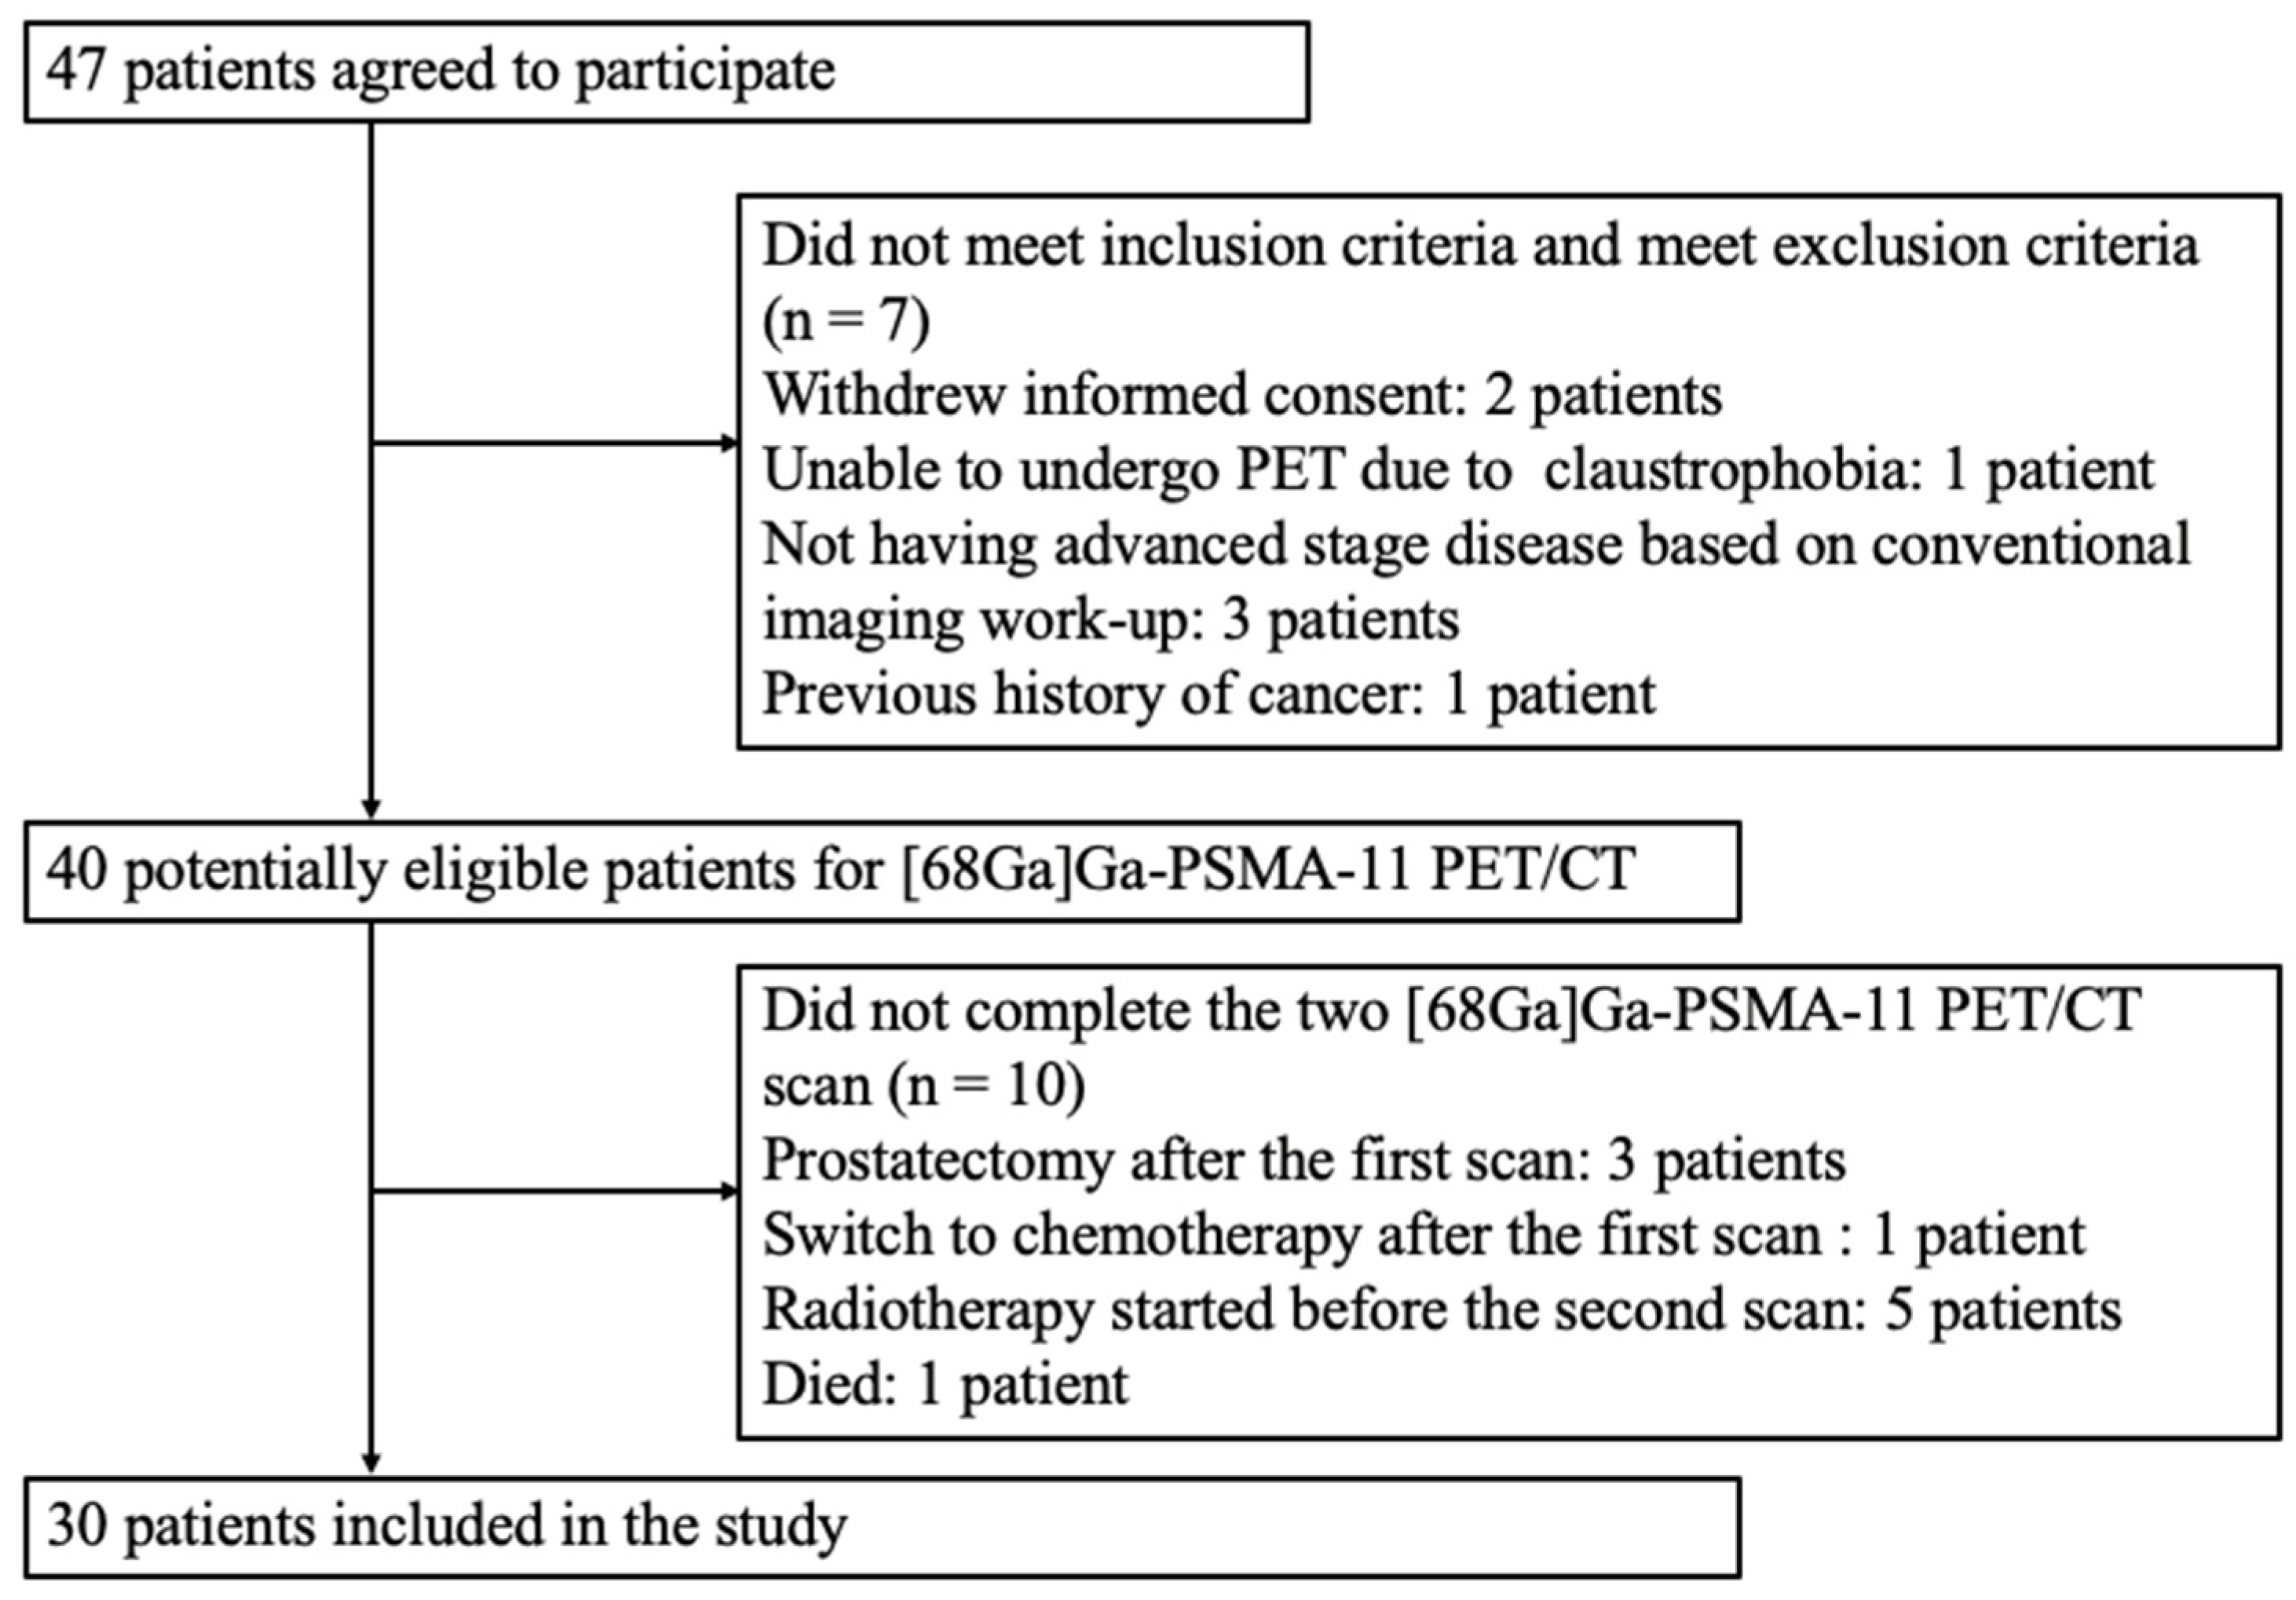

2.2. Patient Selection

3.1. Patient Characteristics and Therapy